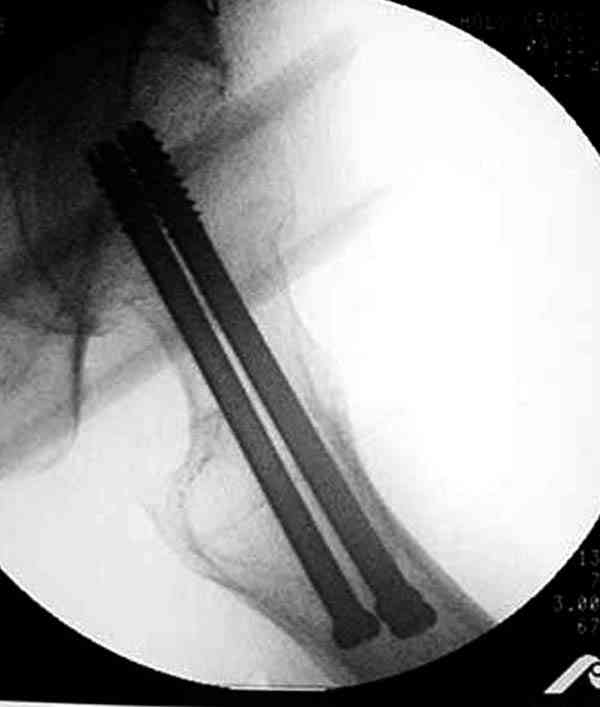

На Московской конференции в ноябре была продемонстрирована удивительная методика профилактического армирования шейки бедра у пациенток с остеопорозом и переломом контрлатеральной шейки в анамнезе.Странно, но дискуссии это сообщение не вызвало.Кто что думает об этом?

Спасибо, Антон. Я автор того сообщения по профилактическому армированию шейки бедренной кости, которое прозвучало на конференции, посвященной 50-летию создания АО. Мне тоже хотелось услышать вопросы по теме. Мы травматологи-ортопеды в первую очередь хирурги, а не терапевты. Почему в вопросе профилактики и лечения остеопороза мы ограничиваемся только консервативными методами лечения? Как можно практически научить больного не получать травмы, когда немало случаев возникновения переломов даже в постели. Первоначально идея армирования ШБК многих, при ком я озвучивал ее, шокировала, затем возникала дискуссия и большинство поддерживали эту идею. Мне бы очень хотелось развернуть дискуссию на странице этого сайта.

Кликните для загрузки файла P3230006.JPG

54KB (56062 bytes)

Уважаемый Антон! У меня было всего три клинических наблюдения, снимки были продемонстрированы на московской конференции. Количества этих снимков хватило для подачи заявки, а затем и получения патента на изобретение. В свое время РОСПАТЕНТ потребовал подтверждения методики клиническими наблюдениями. У одной из больных действительно произошла повторная травма, и произошел подвертельный перелом на стороне армированной шейки бедренной кости (см. снимки). Это подтвердило основную идею изобретения - была сохранена и головка, и армированная шейка бедренной кости. Но тут не обошлось безпроблем. Анестезиологи отказались давать наркоз, а провести остеосинтез под м/а пластиной и винтом DHS не согласилась больная. Дальнейшее лечение скелетным вытяжением. На контр. Рентгенограмме через 2 месяца признаки формирования костной мозоли. Повторных обращений двух других пациентов не было. Для более детальных исследований и выводов необходимо значительно большее количество клинических наблюдений. Такие исследования могли быть проведены в условиях клиник медуниверситета. Напомню, я работаю в травмотделении провинциальной городской больницы. Насчет экспертов страховых компаний, так пусть они выскажут свое мнение. Армирование кости - это плановые операции по желанию больного, какие здесь могут быть противоречия? На армирование все больные, к моему удивлению, согласились довольно легко и сразу, поэтому остеосинтез и армирование были проведены в течение одной операции. С уважением А.М.